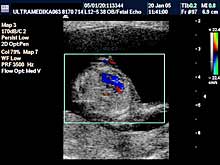

B) II trimestar trudnoće

od 16 do 24

nedelje gestacije

(4 - 6 meseca):

Indikacije za ultrazvučni pregled:

- GENETSKI SONOGRAM

(15-16 nedelja gestacije - 4. mesec):

Otkrivanje ultrazvučnih (soft) markera (markeri koji nisu prisutni u

i trimestru

trudnoće) na postojanje hromozomskih anomalija. Ovaj ultrazvučni

skrining se radi 15- 16 nedelji gestacije u ranom II trimestru

trudnoće. Sam otkriva oko 91% plodova sa aneuploidijama.

- 3D Sono CT SRCA PLODA (fetalna ehokardiografija) Prostorno, vremenska

korelacija ultrazvučnih markera prikazana multiplanarno predstavlja

dopunsku metodu u otkrivanju urođenih srčanih anomalija.

Napomena:

a)

Urođene srčane mane su 6 puta češće od hromozomskih anomalija i

njihova težina često zahteva prekid trudnoće. b)

Ovaj pregled je posebno registrovan za trudnoće koje su prethodno

imale plod sa srčanom manom ili kada u okviru standardnog pregleda

nisu dobijene sve validne ultrazvučne informacije radi pouzdanog

isključenja njihovog postojanja.

Mada je prva procena anatomije srca obavezna u I trimestru trudnoće,

konačna procena se mora završiti od 16 do kraja 24 nedelje gestacije

(6 meseci). Nakon toga procena osnovne anatomije je otežana i

rezervisana je za procenu hemodinamike srca!